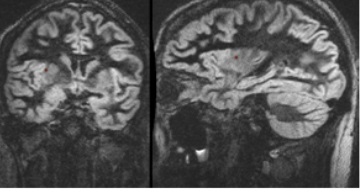

Cube DIR (double inversion recovery) is a single slab, 3D FSE pulse sequence that incorporates two inversion recovery pulses to achieve signal suppression of different tissues. It is used to acquire images with minimized or null signal from either white or grey matter, CSF, and fat.

- Cube DIR is a brain application for improved white matter lesion conspicuity.